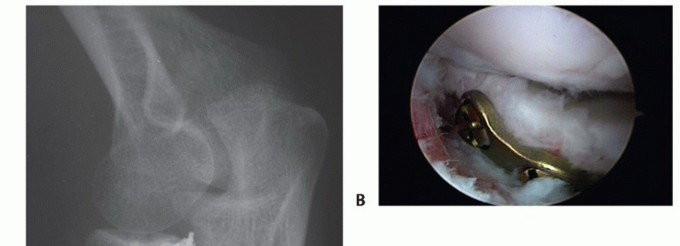

Symptomatic hardware may require secondary removal (FIG 13). Infection

FIG 13 • A. Oblique radiograph demonstrating prominent hardware limiting forearm rotation. B.*

Arthroscopic view in the lateral gutter demonstrating hardware impingement at the PRUJ.

Loss of reduction Nonunion (FIG 14)

- FIG 14 • ORIF of radial neck fracture that went on to nonunion and avascular necrosis.